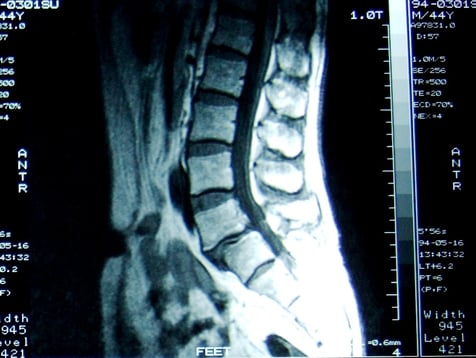

【画像】腰痛テキスト 川端正也著 南江堂 2000年

上の画像は本人のではありませんが、椎間板が変性劣化し腰椎が前方に滑っている画像